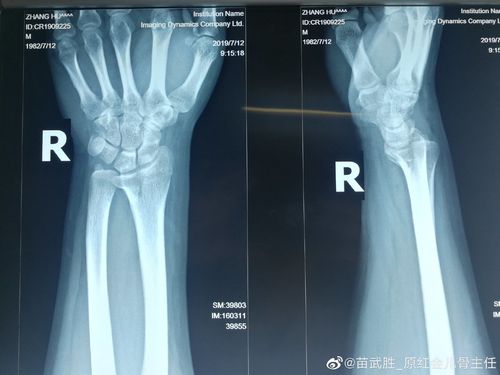

右桡骨远端骨折

右桡骨远端骨折 下尺桡关节脱位

右手桡骨远端骨折